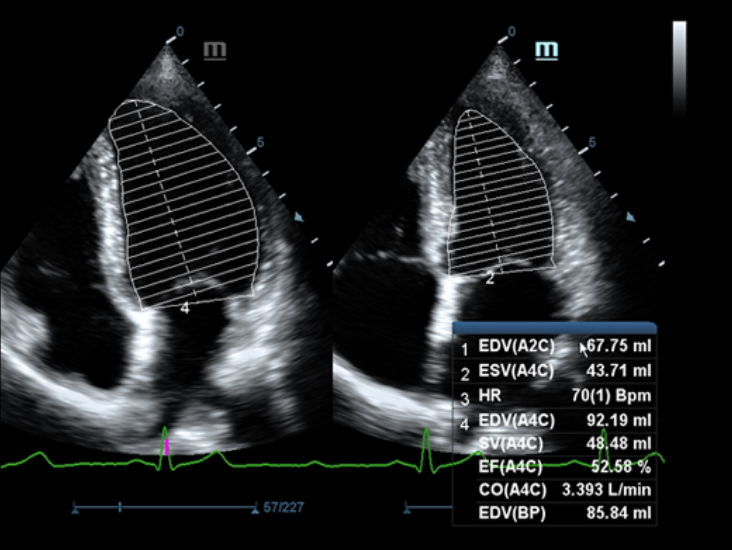

–ě—Ā–Ĺ–ĺ–≤—č–≤–į—Ź—Ā—Ć –Ĺ–į –≥–Ľ—É–Ī–ĺ–ļ–ĺ–ľ –Ņ–ĺ–Ĺ–ł–ľ–į–Ĺ–ł–ł –Ņ–ĺ—ā—Ä–Ķ–Ī–Ĺ–ĺ—Ā—ā–Ķ–Ļ –ļ–Ľ–ł–Ķ–Ĺ—ā–ĺ–≤, –ļ–ĺ–ľ–Ņ–į–Ĺ–ł—Ź Mindray —Ä–į–∑—Ä–į–Ī–ĺ—ā–į–Ľ–į —Ā–ł—Ā—ā–Ķ–ľ—É DC-60 Exp —Ā X-Insight, —á—ā–ĺ–Ī—č –ĺ–Ī–Ķ—Ā–Ņ–Ķ—á–ł—ā—Ć –≤—č—Ā–ĺ–ļ—É—é –Ņ—Ä–ĺ–ł–∑–≤–ĺ–ī–ł—ā–Ķ–Ľ—Ć–Ĺ–ĺ—Ā—ā—Ć –ł —ā–ĺ—á–Ĺ–ĺ—Ā—ā—Ć –≤–ł–∑—É–į–Ľ–ł–∑–į—Ü–ł–ł –≤–ļ—É–Ņ–Ķ —Ā –Ĺ–į–≥–Ľ—Ź–ī–Ĺ–ĺ—Ā—ā—Ć—é, –ł—Ā–ļ–Ľ—é—á–ł—ā–Ķ–Ľ—Ć–Ĺ–ĺ–Ļ –ł–Ĺ—ā–Ķ–Ľ–Ľ–Ķ–ļ—ā—É–į–Ľ—Ć–Ĺ–ĺ—Ā—ā—Ć—é –ł –ĺ–≥—Ä–ĺ–ľ–Ĺ—č–ľ –ĺ–Ņ—č—ā–ĺ–ľ.